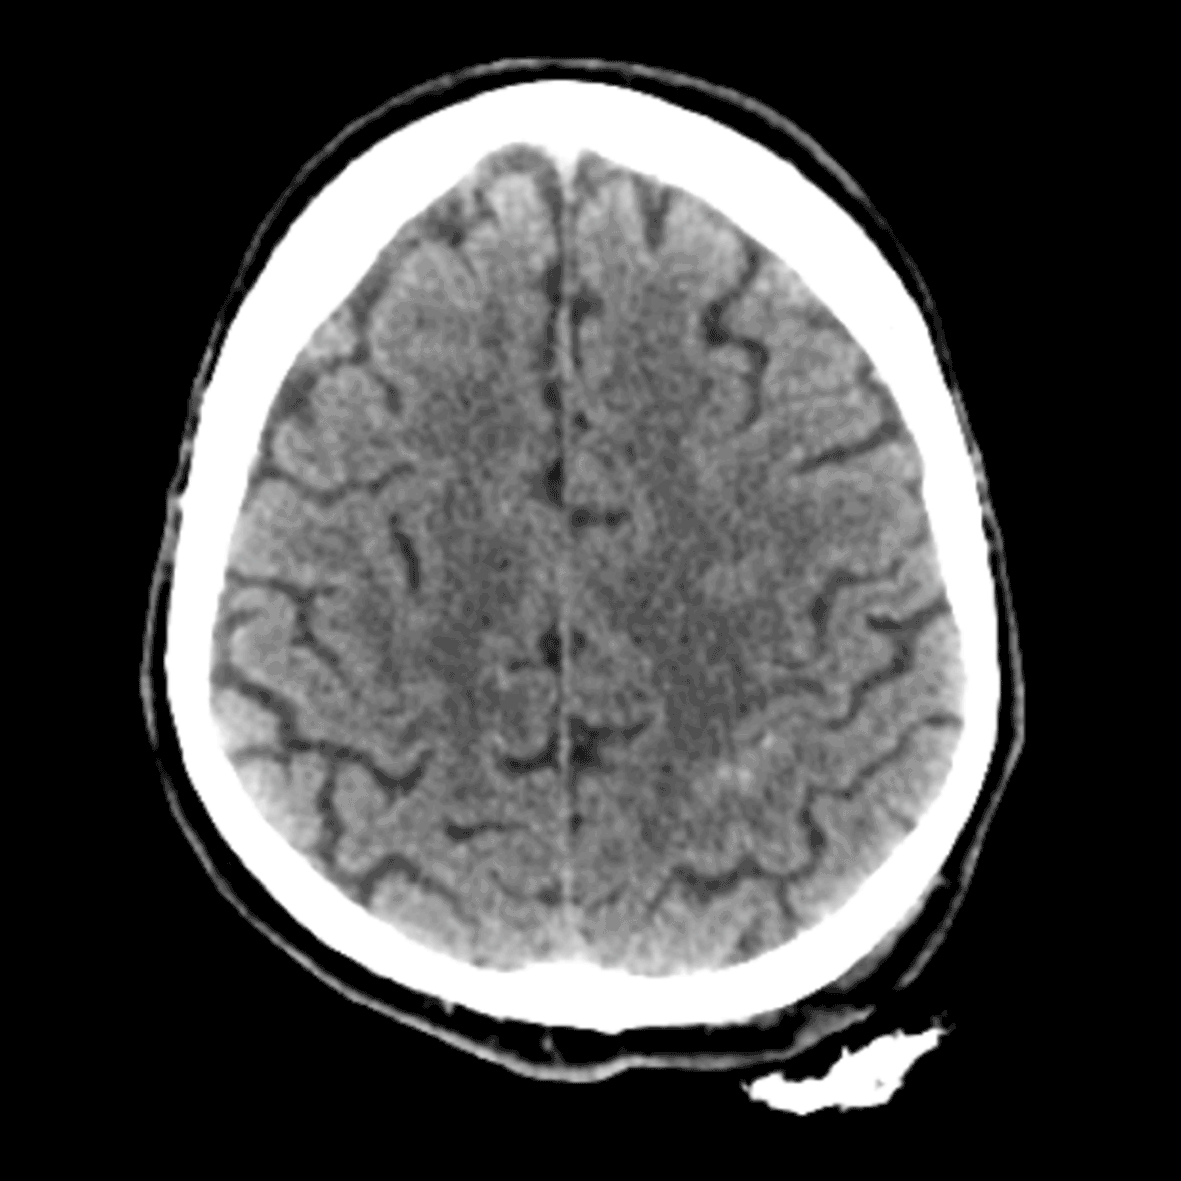

Израильская компания Aidoc объявила о получении разрешения американского FDA (U.S. Food and Drug Administration, Управление по санитарному надзору за качеством пищевых продуктов и медикаментов) на применение в США своего решения на базе искусственного интеллекта (artificial intelligence, AI) для оптимизации рабочих процессов в медицине. Эта система предназначена для помощи радиологам в работе путем установки меток, связанных с острым внутричерепным кровоизлиянием, на сканах головы пациентов, полученных с помощью компьютерной томографии.

Этот продукт, использующий алгоритмы глубокого обучения, является, по словам разработчиков, первым решением, которое предназначено для радиологов и фокусируется на неотложной помощи, когда время имеет определяющее значение.

Алгоритм глубокого обучения, рассказывают разработчики, работает в фоновом режиме и фокусируется на анормальных регионах, а не на какой-то определенной патологии, обеспечивая сортировку изображений и приоритезацию определенных случаев. Все это делается в то время, когда радиолог старается "обработать" большое количество снимков с огромным количеством данных.